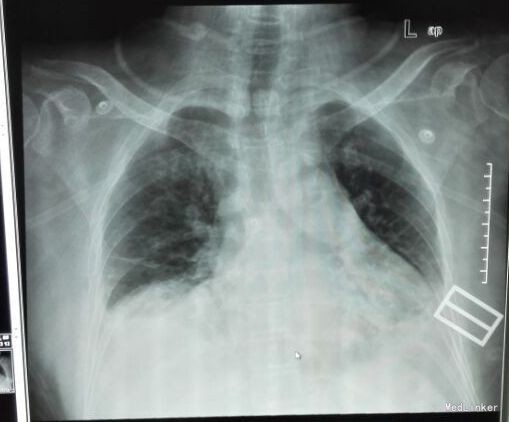

入院查体:体温:36.3℃(X),呼吸:25次/分,脉搏:105次/分,血压:160/80mmHg。神志清楚,平车入室,查体合作。全身皮肤未见皮疹,未见皮下出血点,浅表淋巴结未扪及肿大,咽充血++,扁桃体Ⅰ度肿大,可见滤泡,未见脓点,颈软,气管居中。胸廓无畸形,呼吸稍促,双肺呼吸音粗,右下肺叩诊稍浊,语音震颤增强,双下侧肺野可闻及少许湿啰音,未闻及干啰音,未闻及胸膜摩擦音。心界不大,心率105次/分,律齐,未及杂音,腹膨隆,无压痛、反跳痛,肝脾肋下未触及,肠鸣音减弱,双下肢无水肿。病理征未引出。 门诊辅助检查: 2015-12-13我院急诊查血常规示白细胞计数 14.21 (10E9/L),中性粒细胞比例0.871,淋巴细胞比例 0.049 ,单核细胞比例0.077 ;胸片示:“双下肺炎症、双侧胸腔少量积液;主动脉粥样硬化”,凝血四项PT16.7,急诊血糖:10.75mmol/l,电解质:Na131mmol/l,CL87mmol/l,肝功:Bc8.2umol/l,肾功、心肌酶、三项未见明显异常。